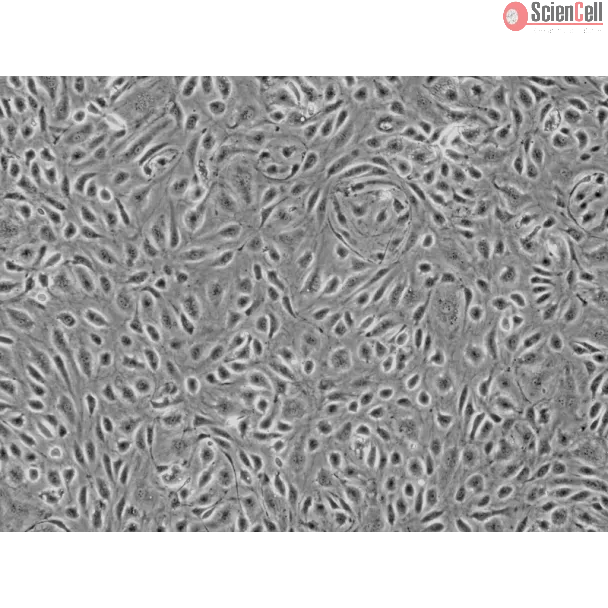

Human Colonic Microvascular Endothelial Cells

Isolated from human colonic tissue. HCoMEC are cryopreserved at passage one and delivered frozen. Each vial contains >5 x 105 cells in 1 ml volume.